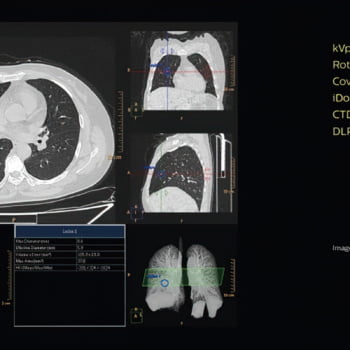

Proporciona uma qualidade de imagem excepcional mesmo para pacientes pequenos

O modo de varredura de 70 kV – o primeiro em um sistema de seu tipo – ajuda a levar o cuidado do paciente a um novo nível, oferecendo escaneamento em baixas doses de pacientes menores e permitindo a proteção de órgãos sensíveis à radiação. Este modo de varredura oferece até 20% de escaneamento em doses mais baixas do que 80 kV.